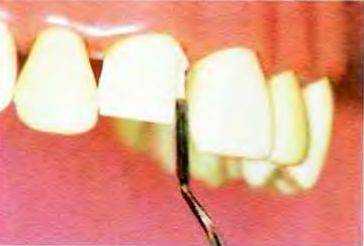

Рис. 13-7. Ориентировочные проточки создают конусным алмазным бором с плоским кончиком

Рис. 13-8. Preston и Miller предложили правила создания ориентировочных проточек. Для правильного выполнения этого этапа необходимо использовать инструменты известного диаметра. определяя глубину погружения относительно поверхности зуба На первом этапе конусный алмазный бор с плоским кончиком располагают параллельно режущей и средней третям вестибулярной поверхности.